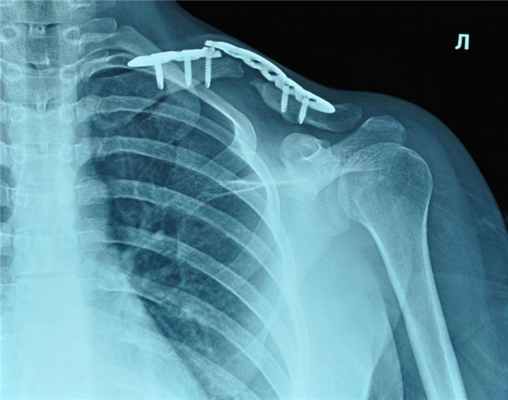

Остеосинтез ключицы

При серьезных травмах с переломами ключицы применяют остеосинтез пластиной. Это соединение и прочная фиксация всех поврежденных костных отломков при помощи специальных элементов фиксации. За счет такого вмешательства пациенты могут быстрее восстановиться без ограничения активности в течение относительно короткого времени.

Ключицы – это две небольшие кости, расположенные над грудной клеткой. Они объединяют ее с костями плеча, соединяя плечевую кость с грудиной. При тяжелых травмах (падения, удар по кости) возможен полный перелом, смещение отломков с нарушением анатомии и функции кости. В этом случае необходим остеосинтез ключицы – оперативное вмешательство, при котором отломки соединяют при помощи специальной пластины и винтов, которые будут удерживать кость на своем месте до полного ее сращения.

Для остеосинтеза используют пластины, спицы, штифты, гвозди Богданова и другие ортопедические конструкции. Врачи выбирают определенный вид, исходя из характера травмы. Для остеосинтеза ключицы чаще всего применяют пластины из титана.

Реконструктивную операцию проводят под общим наркозом. Больной лежит на спине. Под лопатку на стороне поврежденной ключицы подкладывают валики. Далее делают разрез на коже, обнажая участок перелома. Хирурги убирают сгустки крови, накладывают пластину и фиксируют ее винтами. Рану дренируют и ушивают, сверху накладывают стерильную повязку.